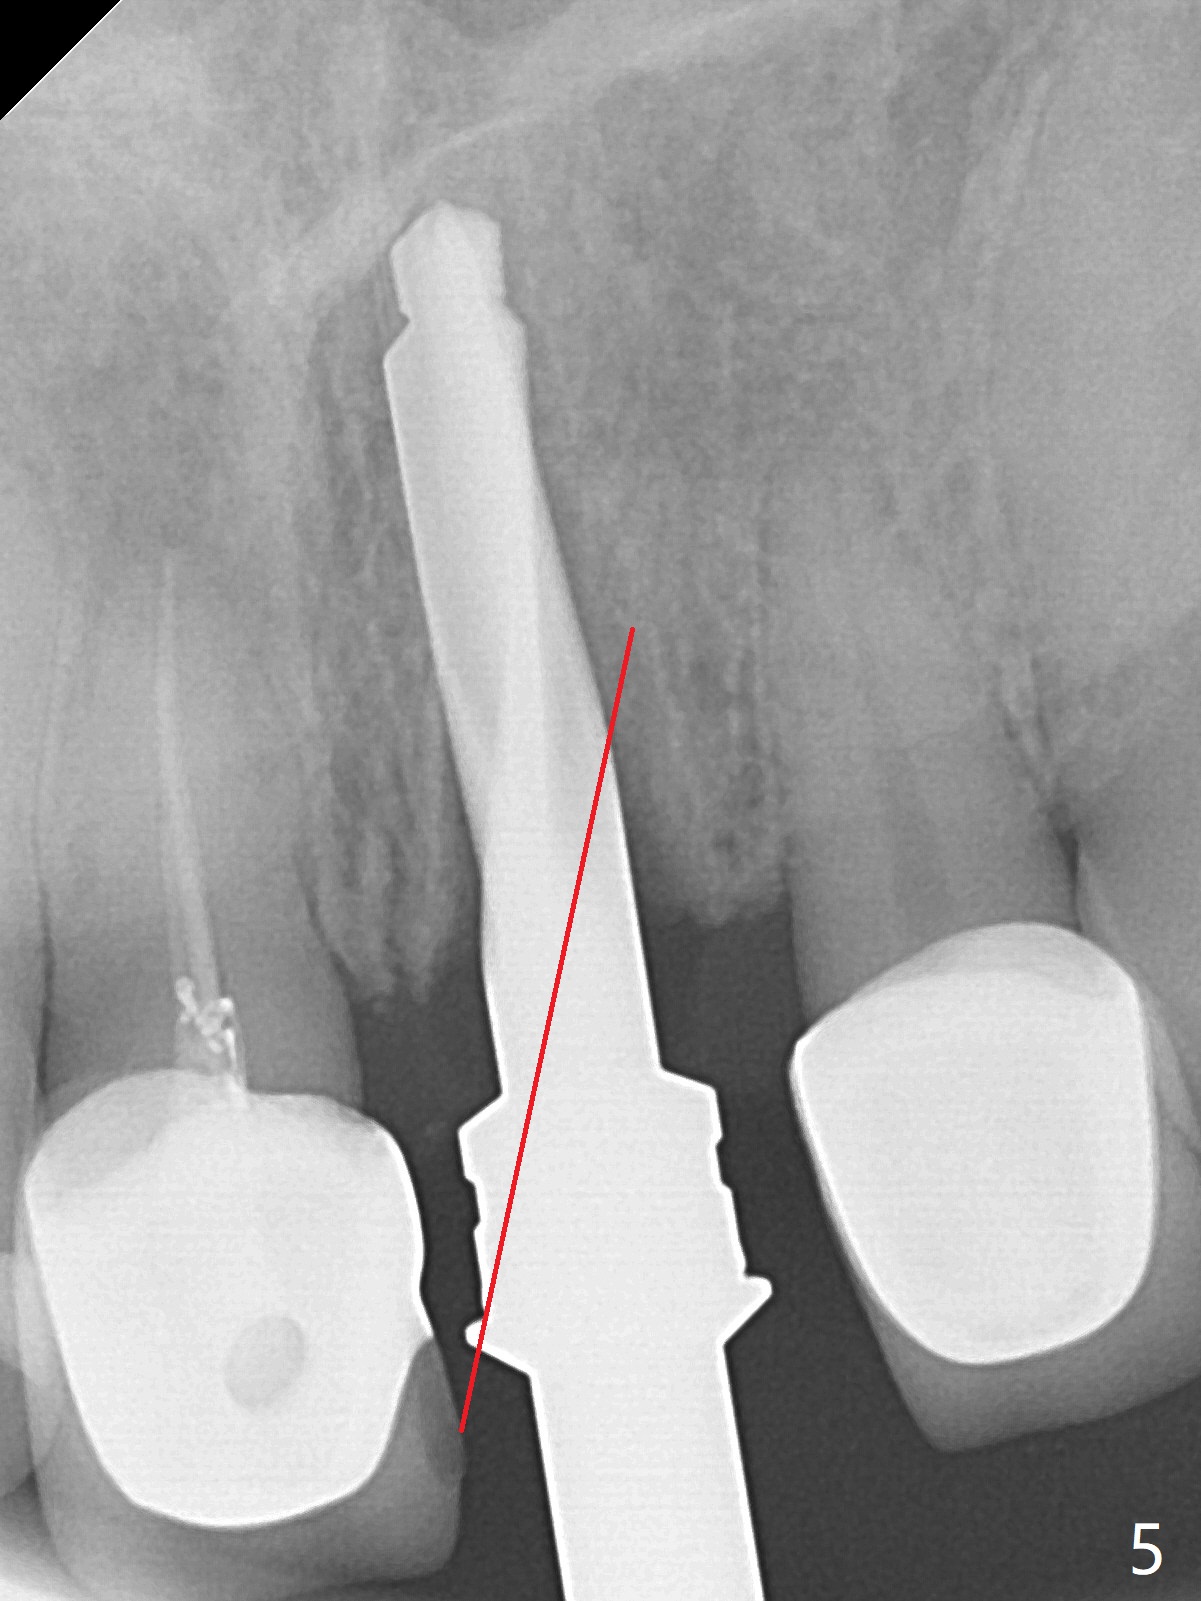

After sectioning the splinted crowns at #8 and 9 (Fig.1,2 (*: open bite)), the tooth #9 is deemed nonsalvageable because of caries and the crown/retainer of #8 is recemented. The trajectory of initial osteotomy is off (Fig.3 (red line: ideal trajectory)). Using Lindamann bur twice does not improve the trajectory (Fig.4,5). It appears that a new osteotomy should be established in the distal wall of the socket (Fig.5 red line (initial entry point and angle), Fig.6). Following sequential osteotomy, a 4x10 mm dummy implant is placed with stability and ~ 3.5 mm apical space (Fig.7 red line). A final implant (4x11.5 mm) is placed subcrestal (except buccal, Fig.8). With further placement of the implant, a 4.5x5.5(3) mm abutment and Vera graft are placed (Fig.9) prior to fabrication of an immediate provisional. In all, a new osteotomy site should be set up when the trajectory is to be changed substantially. There is no gross bone loss 4.5 months postop (Fig.10). There is shade mismatch when a porcelain-fused-Zirconia crown is tried in (Fig.11, as compared to Fig.1). The latter is corrected when a PFM crown is cemented (Fig.12).